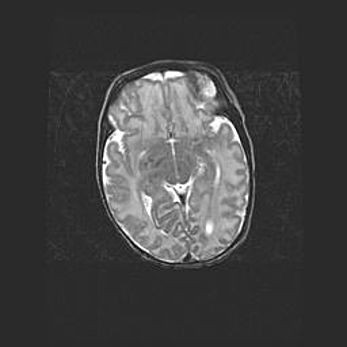

Сообщающаяся гидроцефалия. Кистозная энцефаломаляция головного мозга.

Возраст: 3 месяца 4 дня

Вес: 3100 г

Пол: женский

Окружность головы: 34 см

Срок гестации: 31 неделя

Кистозная энцефаломаляция головного мозга - одна из форм поражения головного мозга в детском возрасте. Характеризуется возникновением множественных и распространённых кист в коре, белом веществе и подкорковых образованиях головного мозга у плодов, новорождённых и детей раннего возраста. Развитие кистозной энцефаломаляции связано с внутриутробной асфиксией и гипотонией, родовой травмой, тромбозом синусов, пороками развития сосудов, инфекциями, сепсисом и другими причинами. Наиболее значимые инфекционные агенты: вирусы простого герпеса, цитомегалии, краснухи, токсоплазмы, энтеробактерии, золотистый стафилококк и другие.